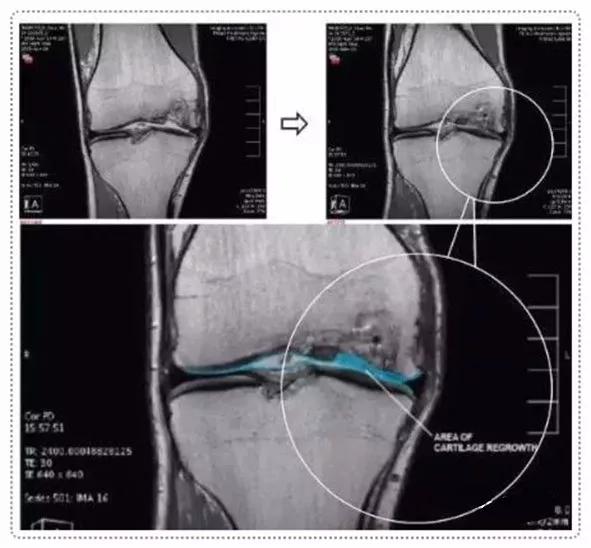

2016年,曾在《干细胞转换医学杂志STEM CELLS TRANSLATIONAL MEDICINE》上报道过,在中外学者共同参与的一项研究中,用人自身来源的软骨细胞结合生物胶原支架,治疗软骨缺损,治疗后随访12个月全部患者的临床评分得到了提高,功能得到改善,疼痛得到缓解。

术后第二次关节镜检查(图a)。在所有4名患者中,移植区域具有保存完好的透明状软骨结构。4例活检标本的组织学检查结果表明,与邻近关节炎软骨相比,修复效果更好。组织显示存在软骨细胞样细胞,以及透明软骨样结构和基质。所有四个活检标本均为无异位钙化和血管化。并且没有发现炎症迹象。